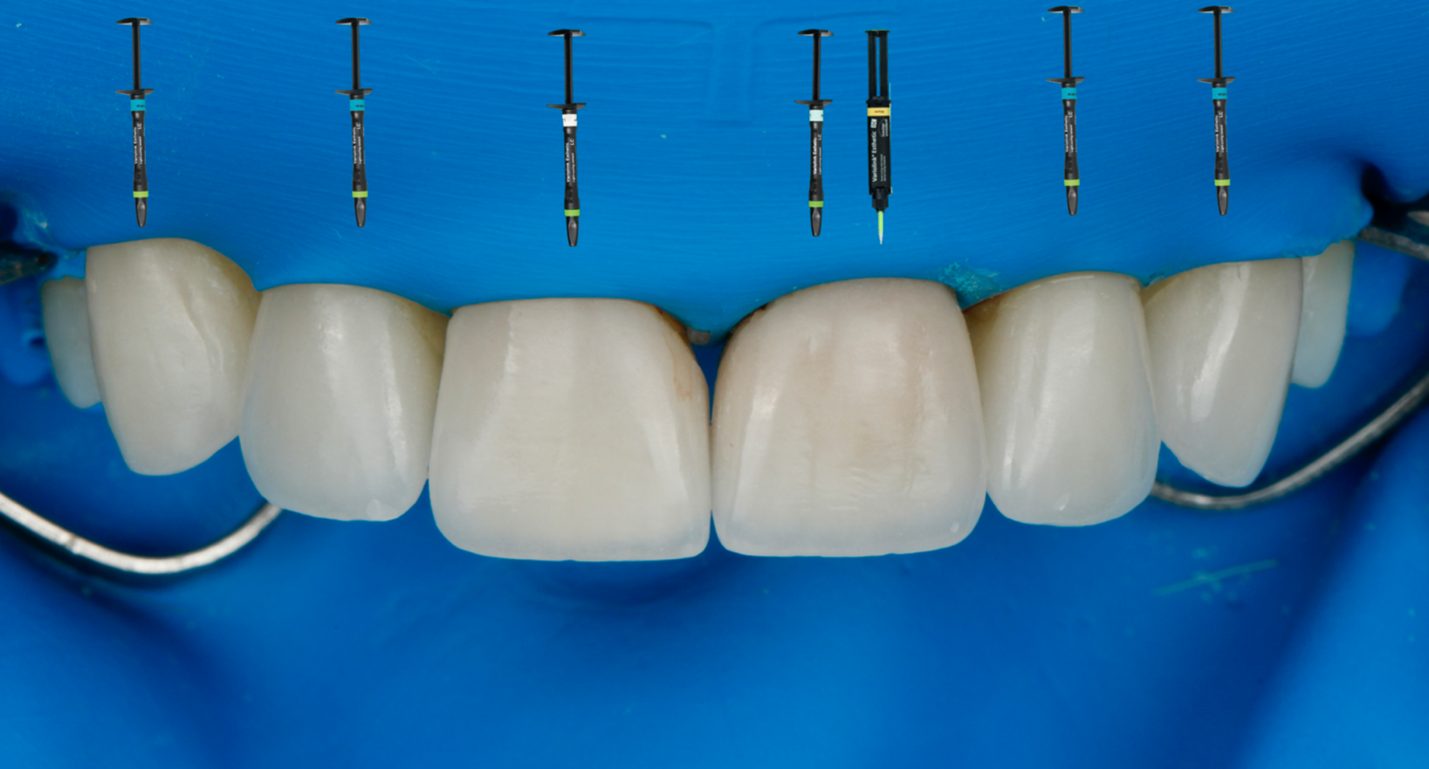

Затем были восстановлены зубы 21 и 11. Колпачок из литийдисиликата был обработан в соответствии с адгезивным протоколом для керамики на основе литийдисиликата, а виниры — согласно протоколу адгезивной фиксации для фельдшпатовидной керамики. Винир на зуб 11 был зафиксирован цементом Variolink Esthetic LC в оттенке Light Plus, а винир на колпачке зуба 21 — цементом Variolink Esthetic LC в оттенке Light (рис. 9). Для боковых резцов и клыков верхней челюсти использовался цемент Variolink Esthetic LC в нейтральном (Neutral) оттенке. Использованные материалы представлены на рисунке 10.

Рис. 9. Фиксация керамических виниров 11 и 21.

Рис. 10. Материалы, использованные для фиксации керамических реставраций в представленном клиническом случае.